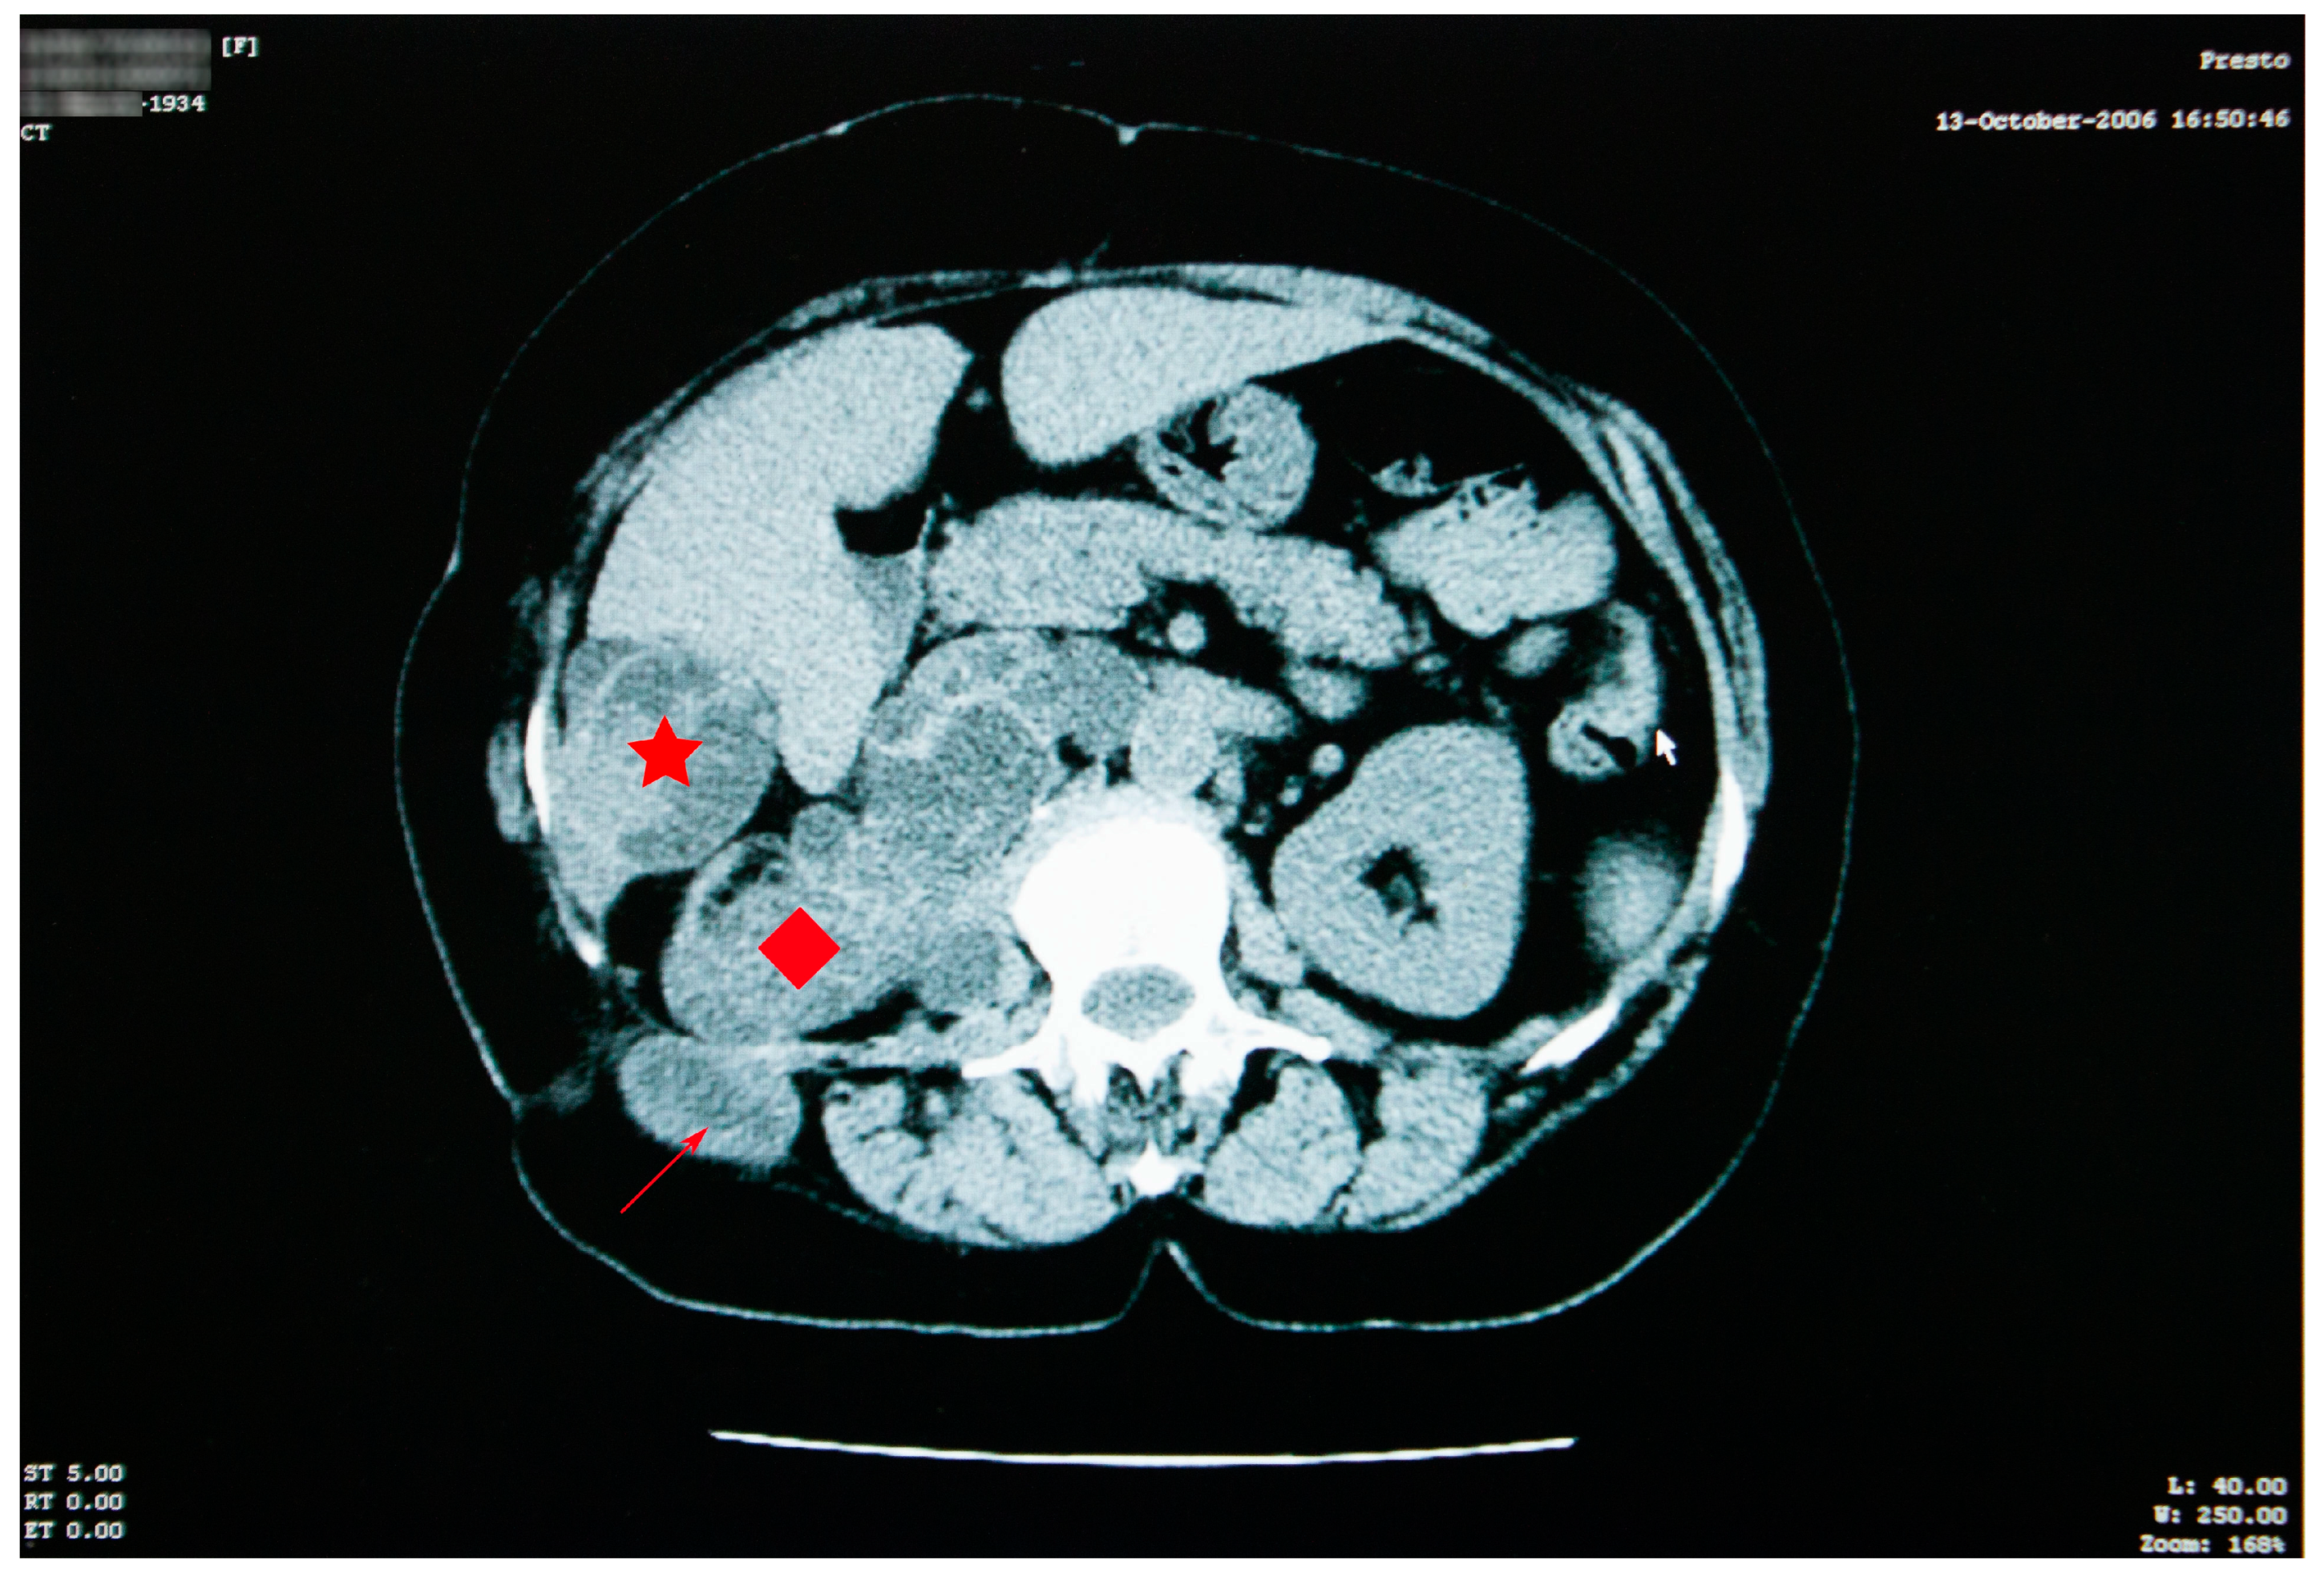

Abdominal imaging revealed multiple cysts, with lots of septa, confluent in the right kidney space, invading the retroperitoneal area down into the right pelvic region, situated between the aorta and the vena cava. Similar types of damage were visible in the sixth right liver segment, as well as the right iliac fossa, and the right paravertebral region (Figure 3).

The right kidney could not be visualized. The psoas muscle, along with the spaces between intestinal loops, had been infiltrated by the same sort of septate cystic masses. A somewhat larger mass, with a size of 45/33 mm, was observed adjacent to the bowel on the right side. The specific serology was intensely positive.

Figure 3. Abdominal CT scan showing multiple cysts, confluent in the right kidney space (red diamond), invading the retroperitoneal area, in the sixth right liver segment (star) and in the right iliac fossa and right paravertebral area (arrow).